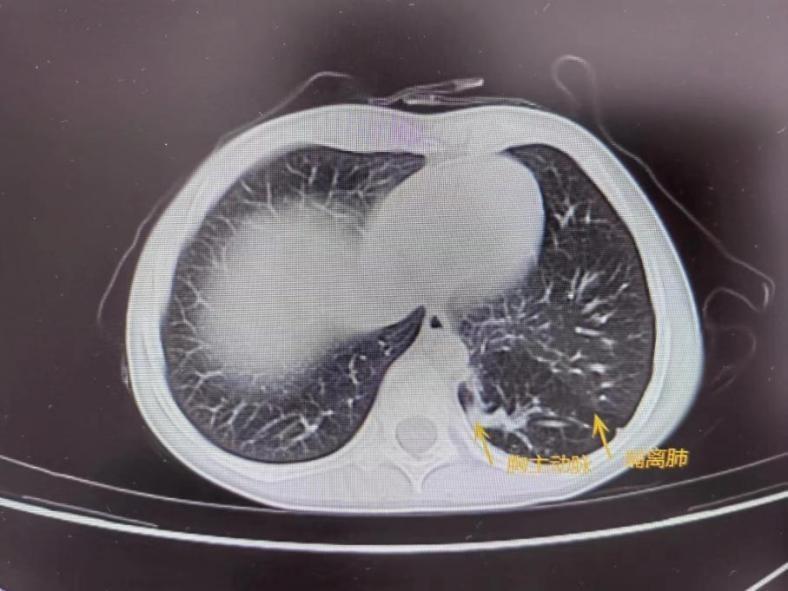

术前肺部CT提示左肺下叶叶内型肺隔离症,病灶动脉血供来自于胸主动脉近膈肌段。开胸手术无疑是提高手术安全性的一种选择。但是由于多多年龄尚小,开放手术创伤巨大且术后切口瘢痕严重,会给多多幼小的心灵留下不可磨灭的创伤。因此,经过多学科充分的术前准备和讨论,最终曹主任为多多制定了微创治疗方案——单孔胸腔镜下左侧叶內型隔离肺切除术。

先天性肺隔离症又称支气管肺隔离症,为先天性肺发育畸形。肺隔离症占肺部疾病的0.15%-6.4%。临床特点为存在异常动脉供血,主要来自体循环供血,多为胸主动脉及腹主动脉,主要分为叶内型肺隔离症、叶外型肺隔离症和混合型肺隔离症。治疗方法首选手术切除病变肺组织。